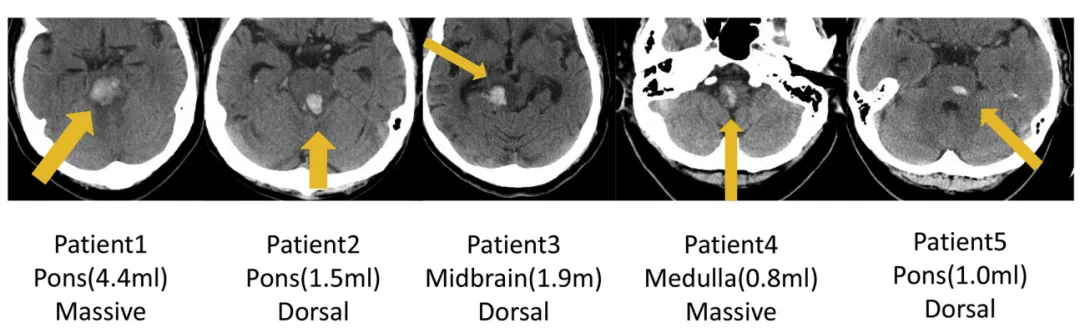

INC巴教授2018年发表论文《Surgical Treatment for Primary Brainstem Hemorrhage to Improve Postoperative Functional Outcomes》中讨论了5例接受手术治疗的原发性脑干出血患者,以及手术治疗改善术后功能结果的能力,分析了术后1周的术后功能结果(表3)和出院后6个月的改良Rankin量表评分(表4),结果显示均有所好转。

图:5例原发性脑干出血(PBH)患者的轴位CT影像。